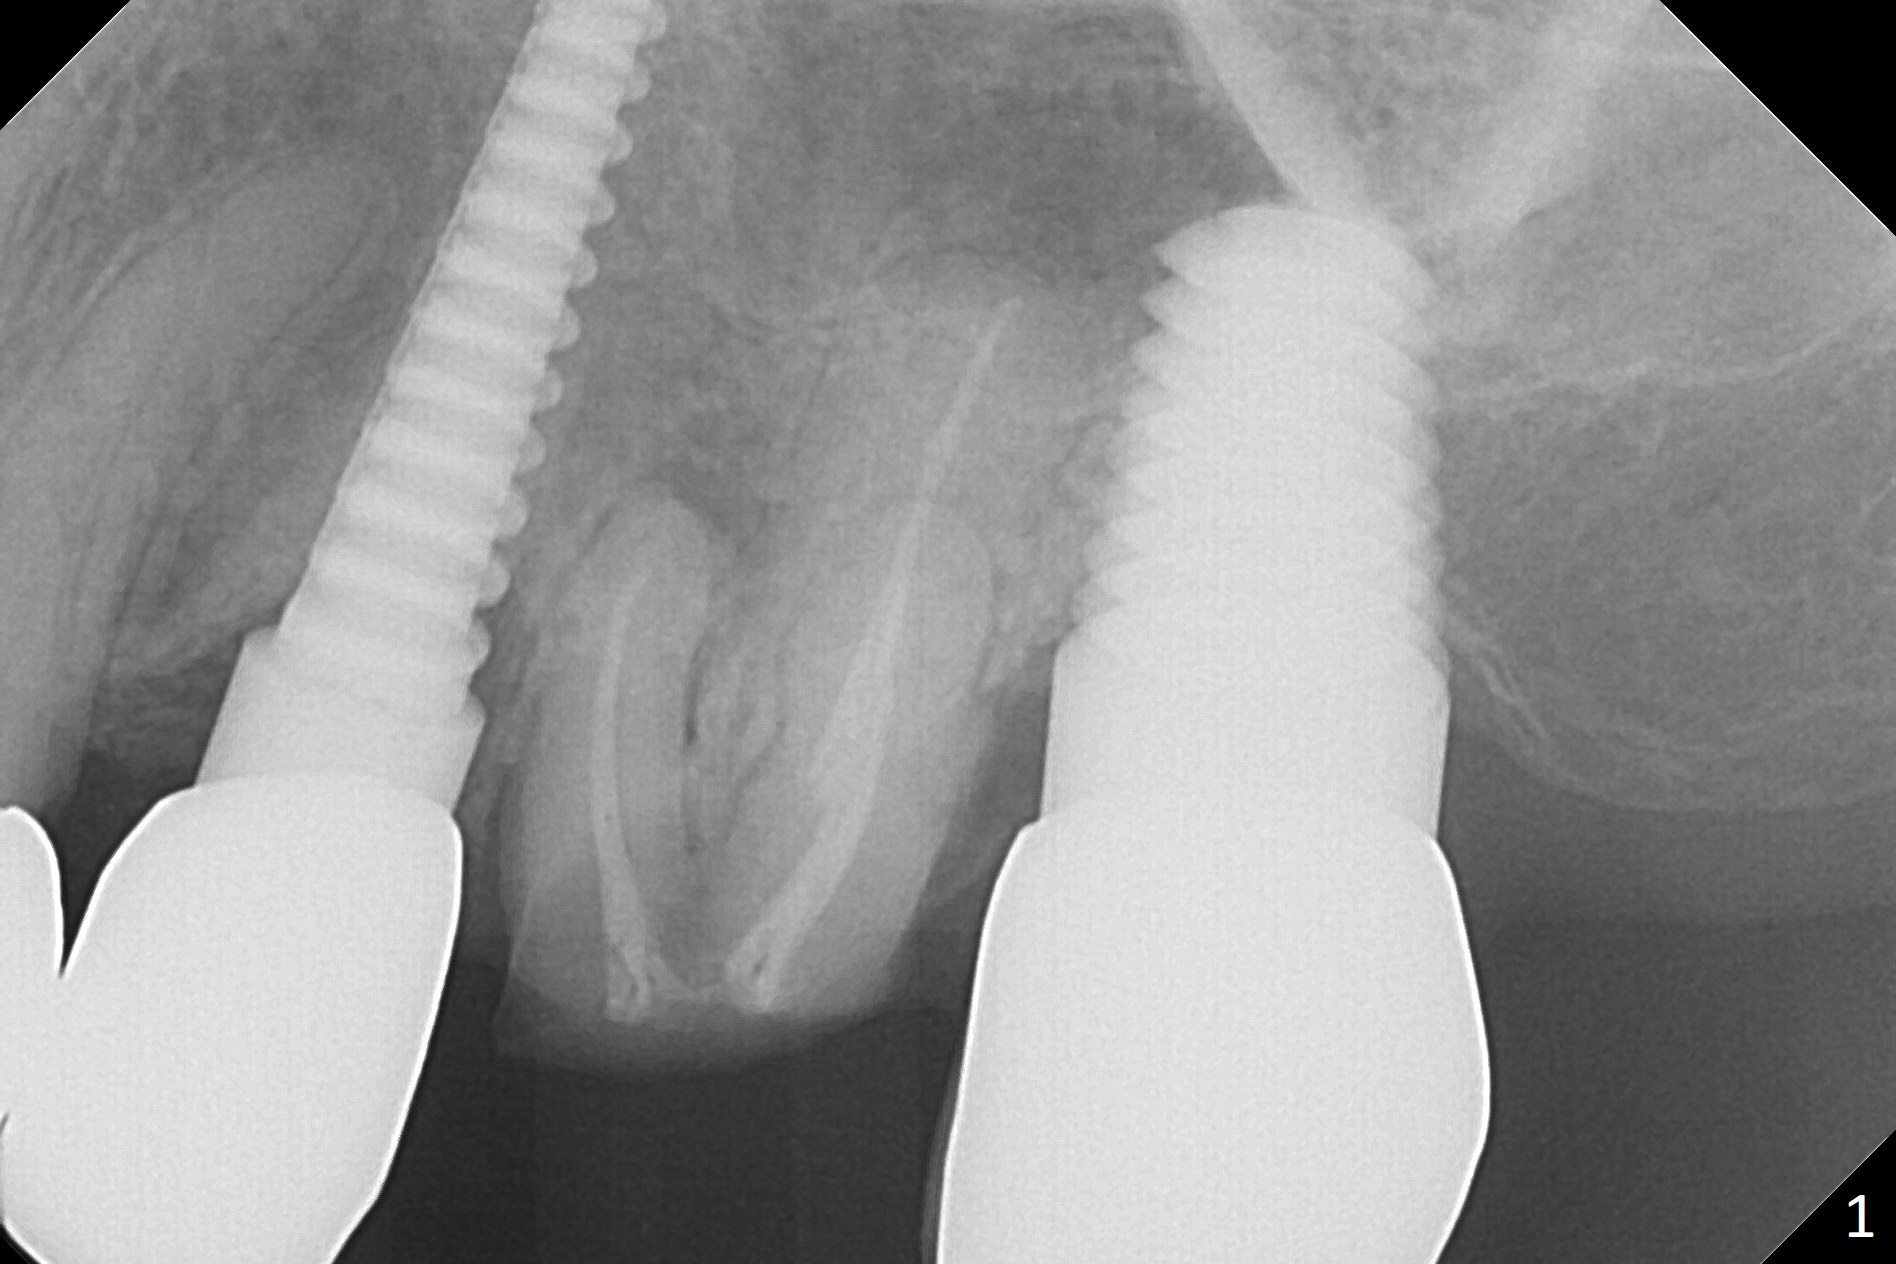

A 70-year-old woman fractures the crown at #14 (Fig.1). A 5x11 mm implant will be placed at the septum (Fig.2). Osteotomy depth can be determined using bony (Fig.3 with stopper) or gingival (Fig.4,5 with vision) landmark. The CT was taken 5 years earlier. Sagittal (Fig.6) and axial (Fig.7) sections confirm suitability of the 5x11 mm implant for the site. Prepare surgical handpiece for sectioning the tooth for extraction. After drills, use Magic Expanders for sinus lift. Place Vanilla Graft prior to dummy implant(s). A bone-level implant crown may be easier to be repaired if the proximal contact is not ideal.